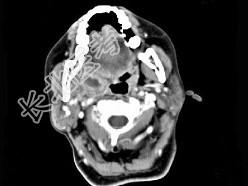

- 单项选择题女,52岁, 咽喉部疼痛半个月,伴低热, CT如图所示,最可能的诊断是 ( )

A、咽旁脓肿

B、咽部神经鞘瘤

C、鼻咽纤维血管瘤

D、咽旁淋巴瘤

E、咽旁转移瘤